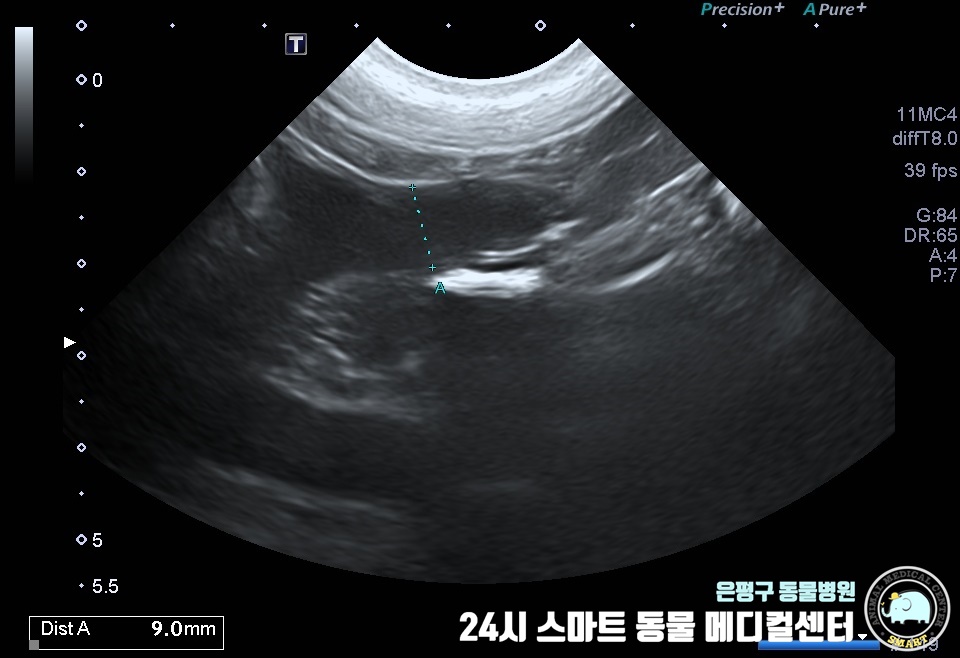

생식기에 황농이 확인되어 자궁경부측의 감염 가능성이 있는 것으로 보이며, 검사 결과 자궁축농증으로 확인되었습니다.

질 주변의 고름이 관찰되었으며 자궁부에서는 약간의 확장과 출혈이 관찰되었습니다.